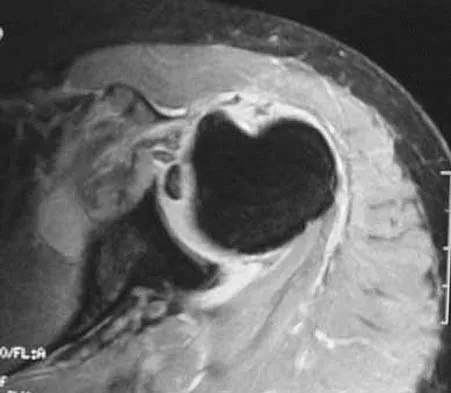

A 29-year-old man who lifts weights states that he injured his left shoulder while performing a bench press 2 days ago. The following morning he noted ecchymosis and swelling in the left chest wall. Examination reveals ecchymosis and tenderness and deformity in the left anterior chest wall and axillary fold that is accentuated with resisted adduction of the arm. Passive range of motion beyond 90 degrees of forward flexion and 45 degrees of external rotation is extremely painful. Glenohumeral stability is difficult to assess because of severe guarding. Figure 29 shows an MRI scan. Management should consist of

Explanation

Rupture of the pectoralis major tendon most commonly occurs during bench pressing. Wolfe and associates have shown that the most inferiorly located fibers of the sternal head lengthen disproportionately during the final 30 degrees of humeral extension during the bench press. This creates a mechanical disadvantage in the final portion of the eccentric phase of the lift; with forceful flexion of the shoulder these maximally stretched fibers may rupture. In most patients, particularly in young athletes, the treatment of choice is anatomic repair of the ruptured tendon to its insertion in the proximal humerus either with suture anchors or transosseous sutures. Following surgery, most patients experience a near normal return of strength and significant improvement in the cosmetic appearance of the deformity. While more technically challenging, repair of chronic rupture is possible and is indicated in some patients. Wolfe SW, Wickiewicz TL, Cavanaugh JT: Ruptures of the pectoralis major muscle: An anatomic and clinical analysis. Am J Sports Med 1992;20:587-593.